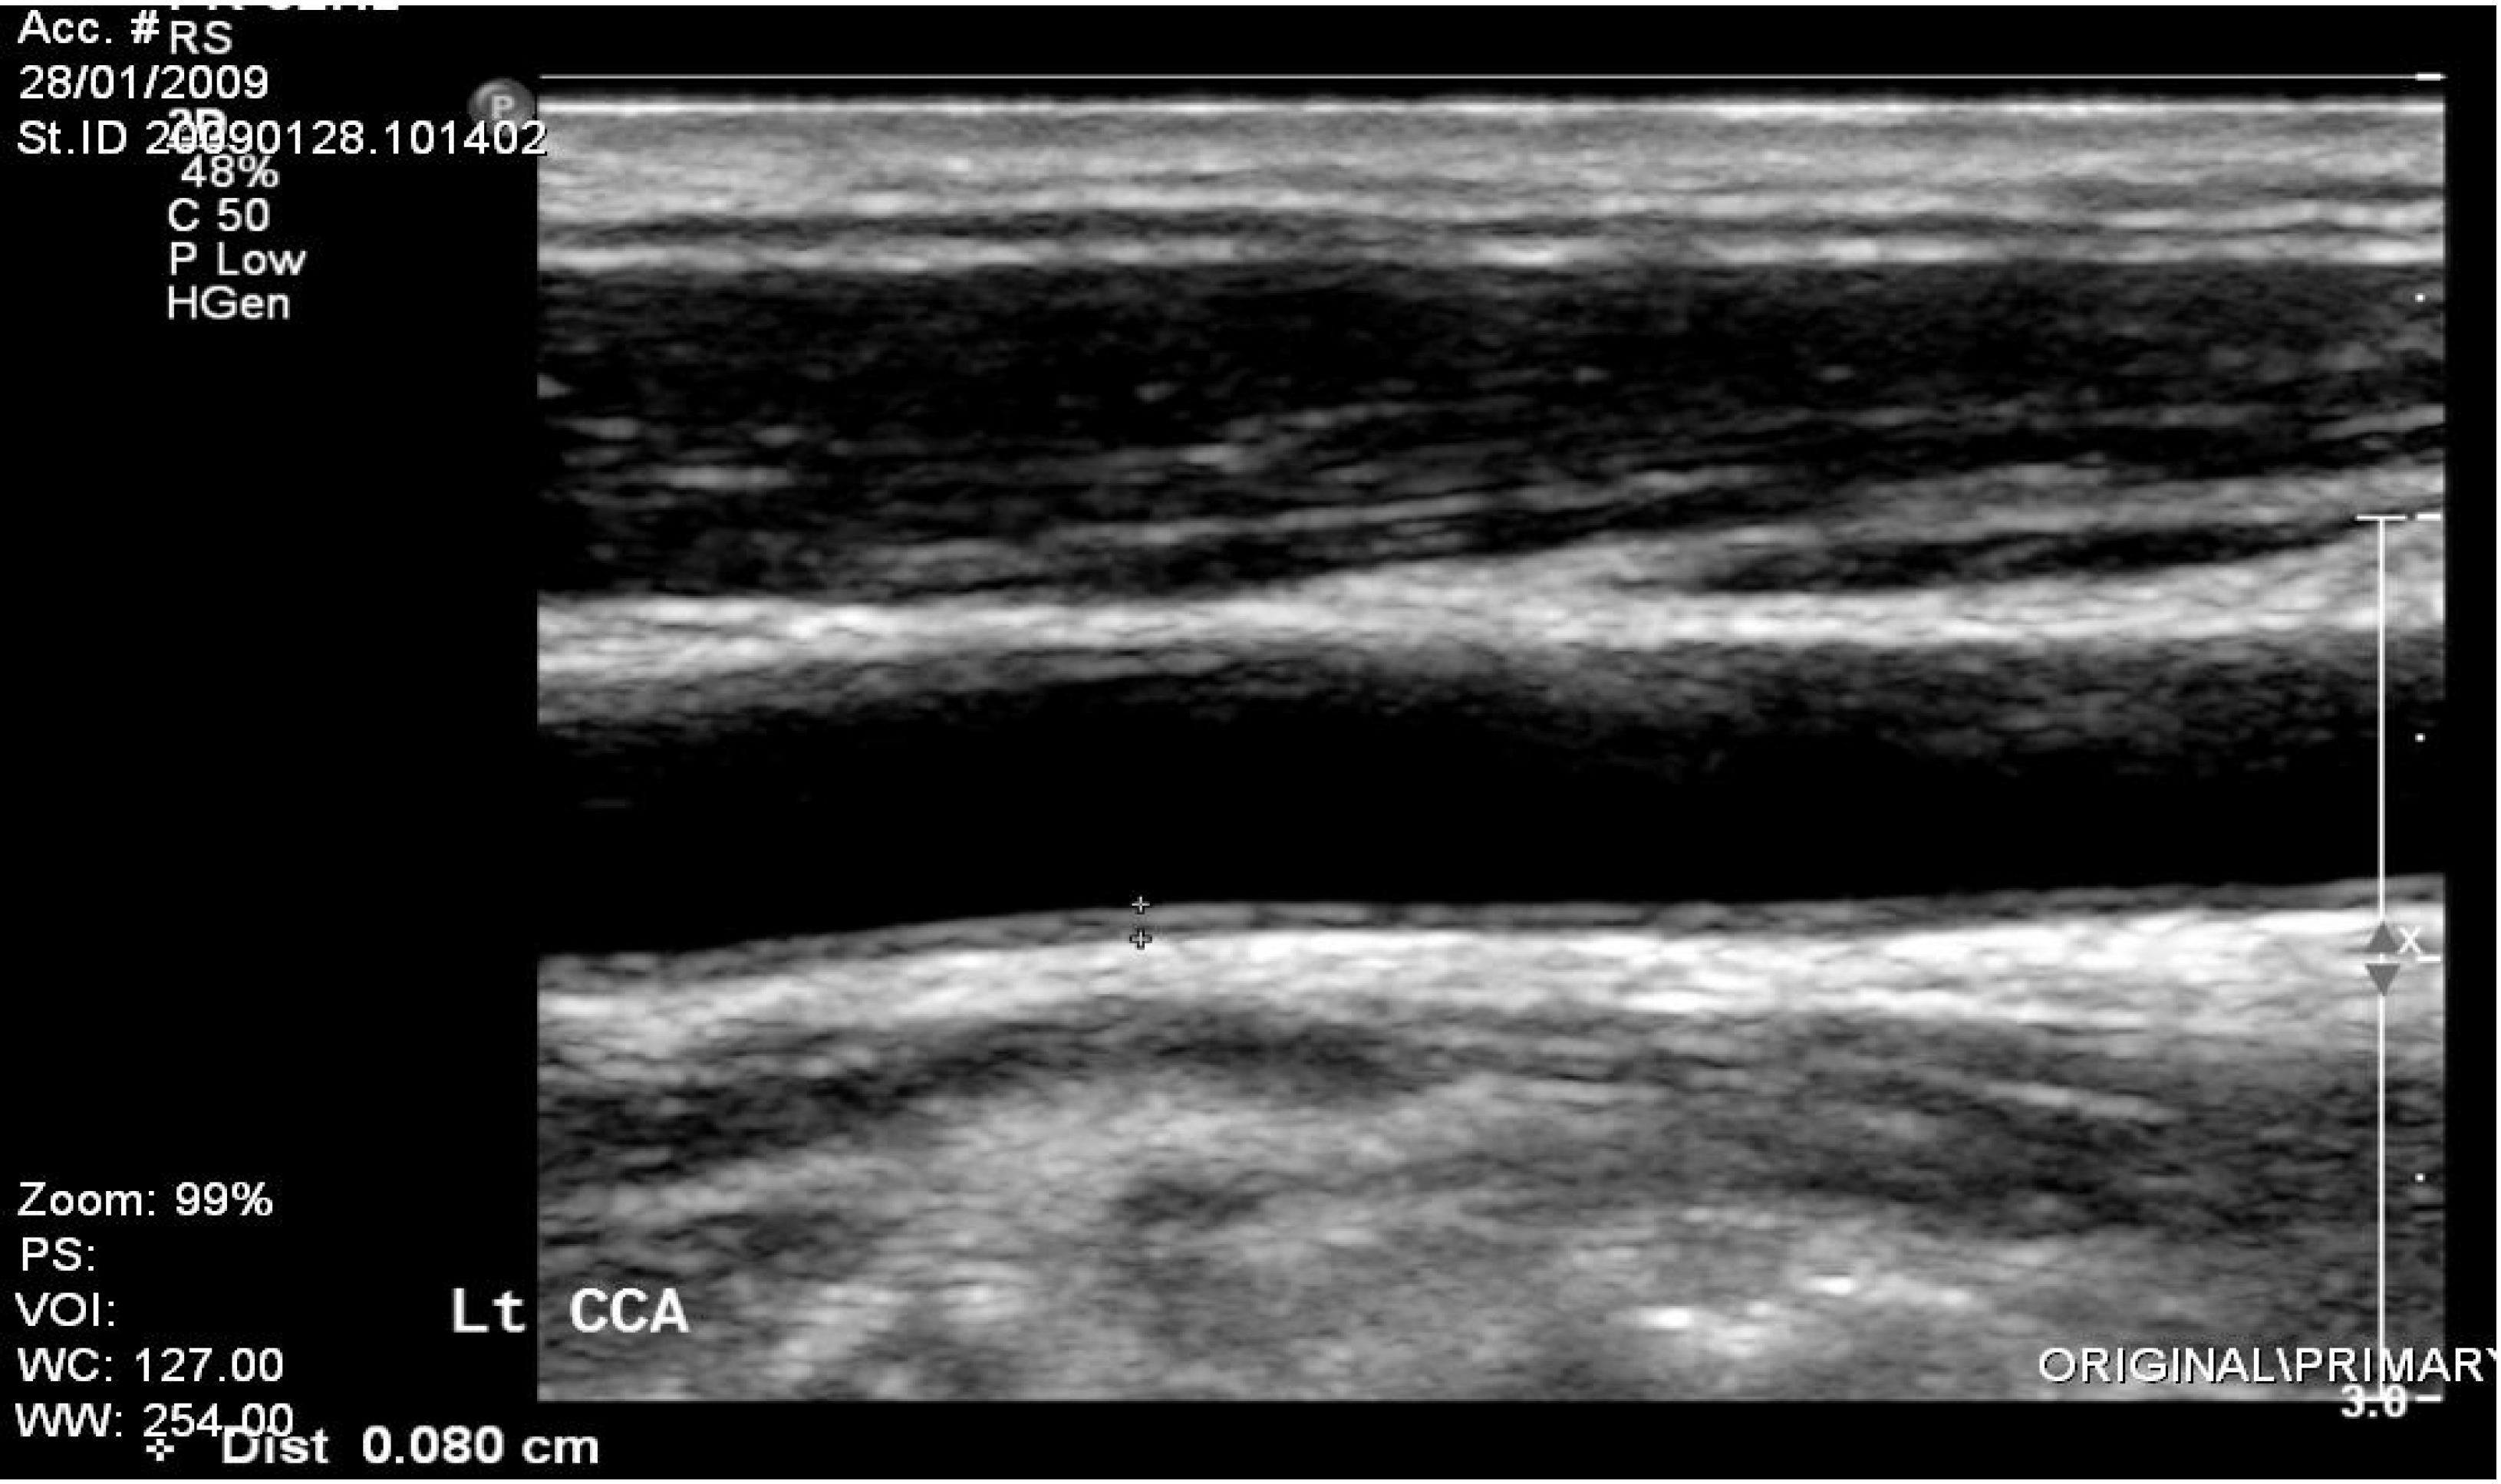

| IMT, mean Right Carotis (mm) | 0.90 ± 0.19 | 0.8 ± 0.10 | 0.03 |

| Left Carotis (mm) | 0.98 ± 0.30 | 0.8 ± 0.10 | 0.27 |

| Mean Carotis Plaques% | 60% | 40% | 0.01 |